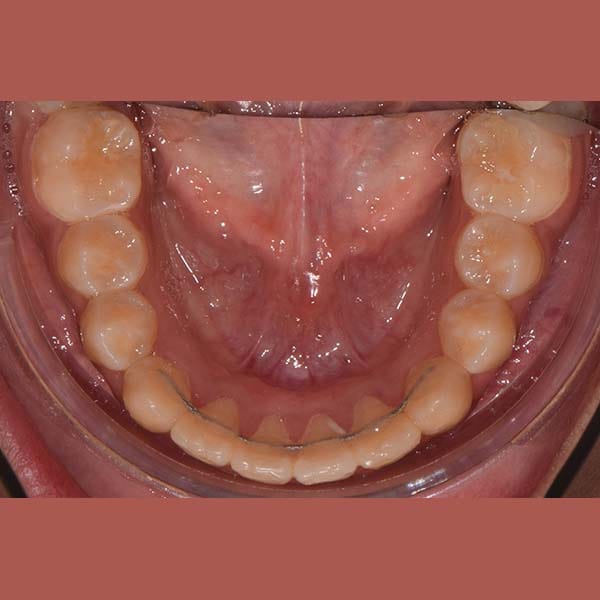

بعد شرح أن قلع الأسنان يكون ضرورياً أحياناً، وبعد الفحص الدقيق، طمأن الدكتور خالد الكاتب الأم بأنه لحسن الحظ، حالة ابنتها تسمح بالعلاج دون قلع. اعتمدت الخطة على توسيع الفكين لفتح مسافة كافية لرصف الأسنان. تم اختيار تقويم الدايمون (ذاتي الربط) لهذه المهمة، حيث يعتبر مثالياً لهذا النوع من المعالجات التي تتطلب توسيعاً فعالاً.

كما تظهر الصور، نجحت الخطة العلاجية في رصف الأسنان بشكل ممتاز وتحقيق ابتسامة جميلة ومتناسقة. وكالعادة، أصبح بإمكان صديقتنا الشابة أن تبتسم لوالدتها ولكل من حولها بثقة وسعادة.